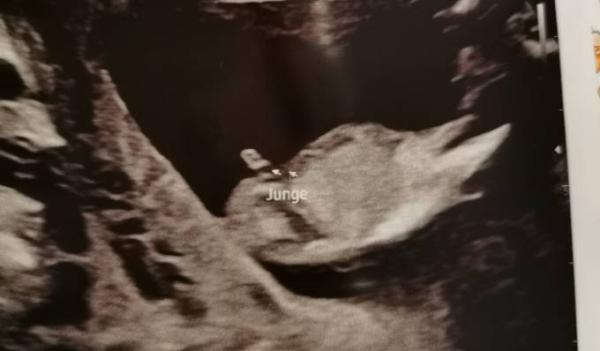

Bei 12+1 wurde ein Junge vermutet, für mich sieht es nach Nabelschnur aus

Also bei meinen Bildern sieht die Nabelschnur immer so aus als wären es aneinandergereihte Bläschen finde es aber für 12+1 schon einen riesen Pimmel aber man weiß ja nie

Also nach Nabelschnur sieht es für mich nicht aus